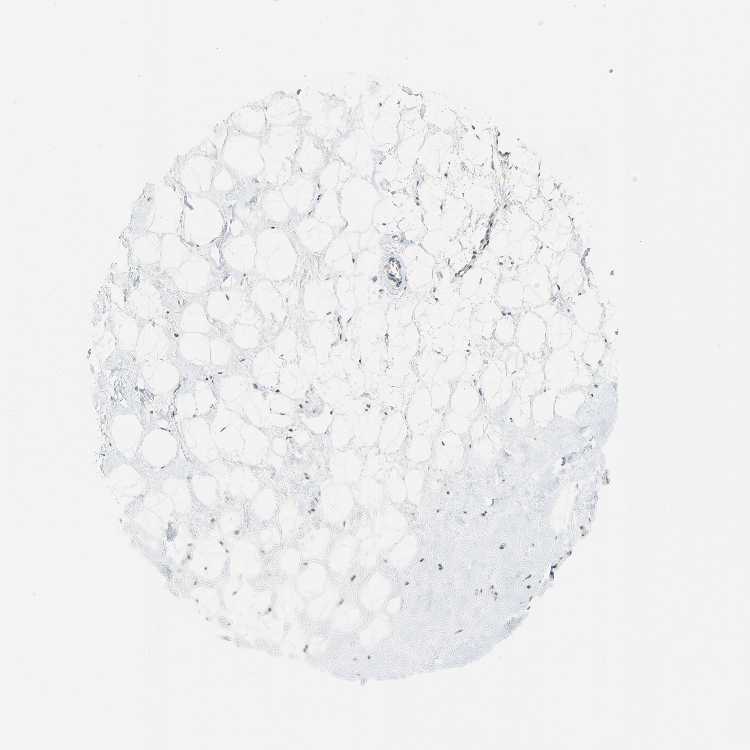

BREAST - Antibody stainingi

Antibody staining in the annotated cell types in the current human tissue is reported as not detected, low, medium, or high, based on conventional immunohistochemistry profiling in selected tissues. This score is based on the combination of the staining intensity and fraction of stained cells.

Each image is clickable and will lead to virtual microscopy that enables deeper exploration of all samples and also displays staining intensity scores, fraction scores and subcellular localization as well as patient and tissue information for each sample.

Antibody HPA024258Antibody HPA058593Antibody CAB004670

Adipocytes Not detectedLowNot detected

Glandular cells LowNot detectedNot detected

Myoepithelial cells Not detectedNot detectedNot detected